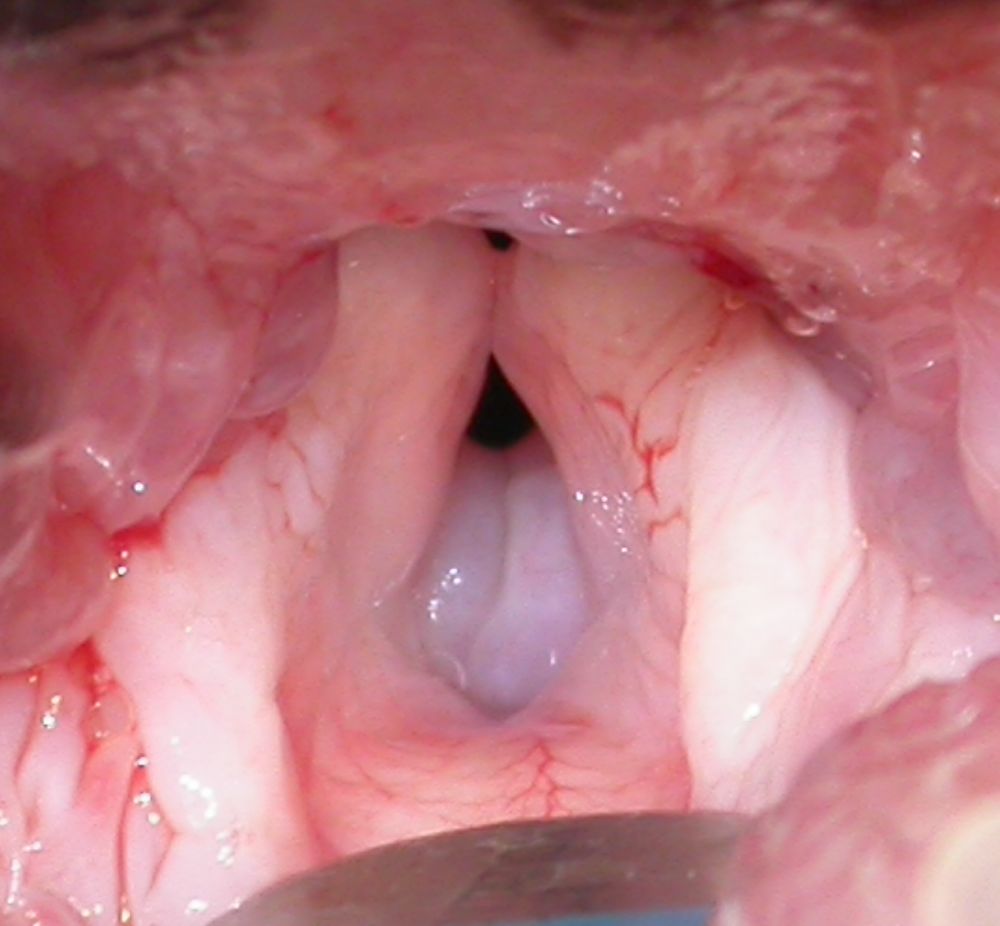

The study recorded a huge rise in soft tissue surgical procedures from 659 in 2008 to 1,001 in 2018 that has largely been driven by the increased requirement of these specialist RVC surgeons to offer care for flat-faced dogs. Flat-faced dogs describe those types of dogs that are deliberately designed and bred not to have a natural long nose. Sadly, these dogs lose much of the natural function of a long nose to ensure easy breathing, enable sleep and to cool the dog, and therefore many flat-faced dogs suffer severe breathing problems. Procedures specifically to manage brachycephalic obstructive airway syndrome (BOAS), the serious breathing condition affecting flat-faced breeds, rose considerably from 16 surgeries in 2008 to 131 in 2018, representing an increase of 813%.

- Almost half (45%) of all BOAS surgeries performed in 2018 were on French Bulldogs.